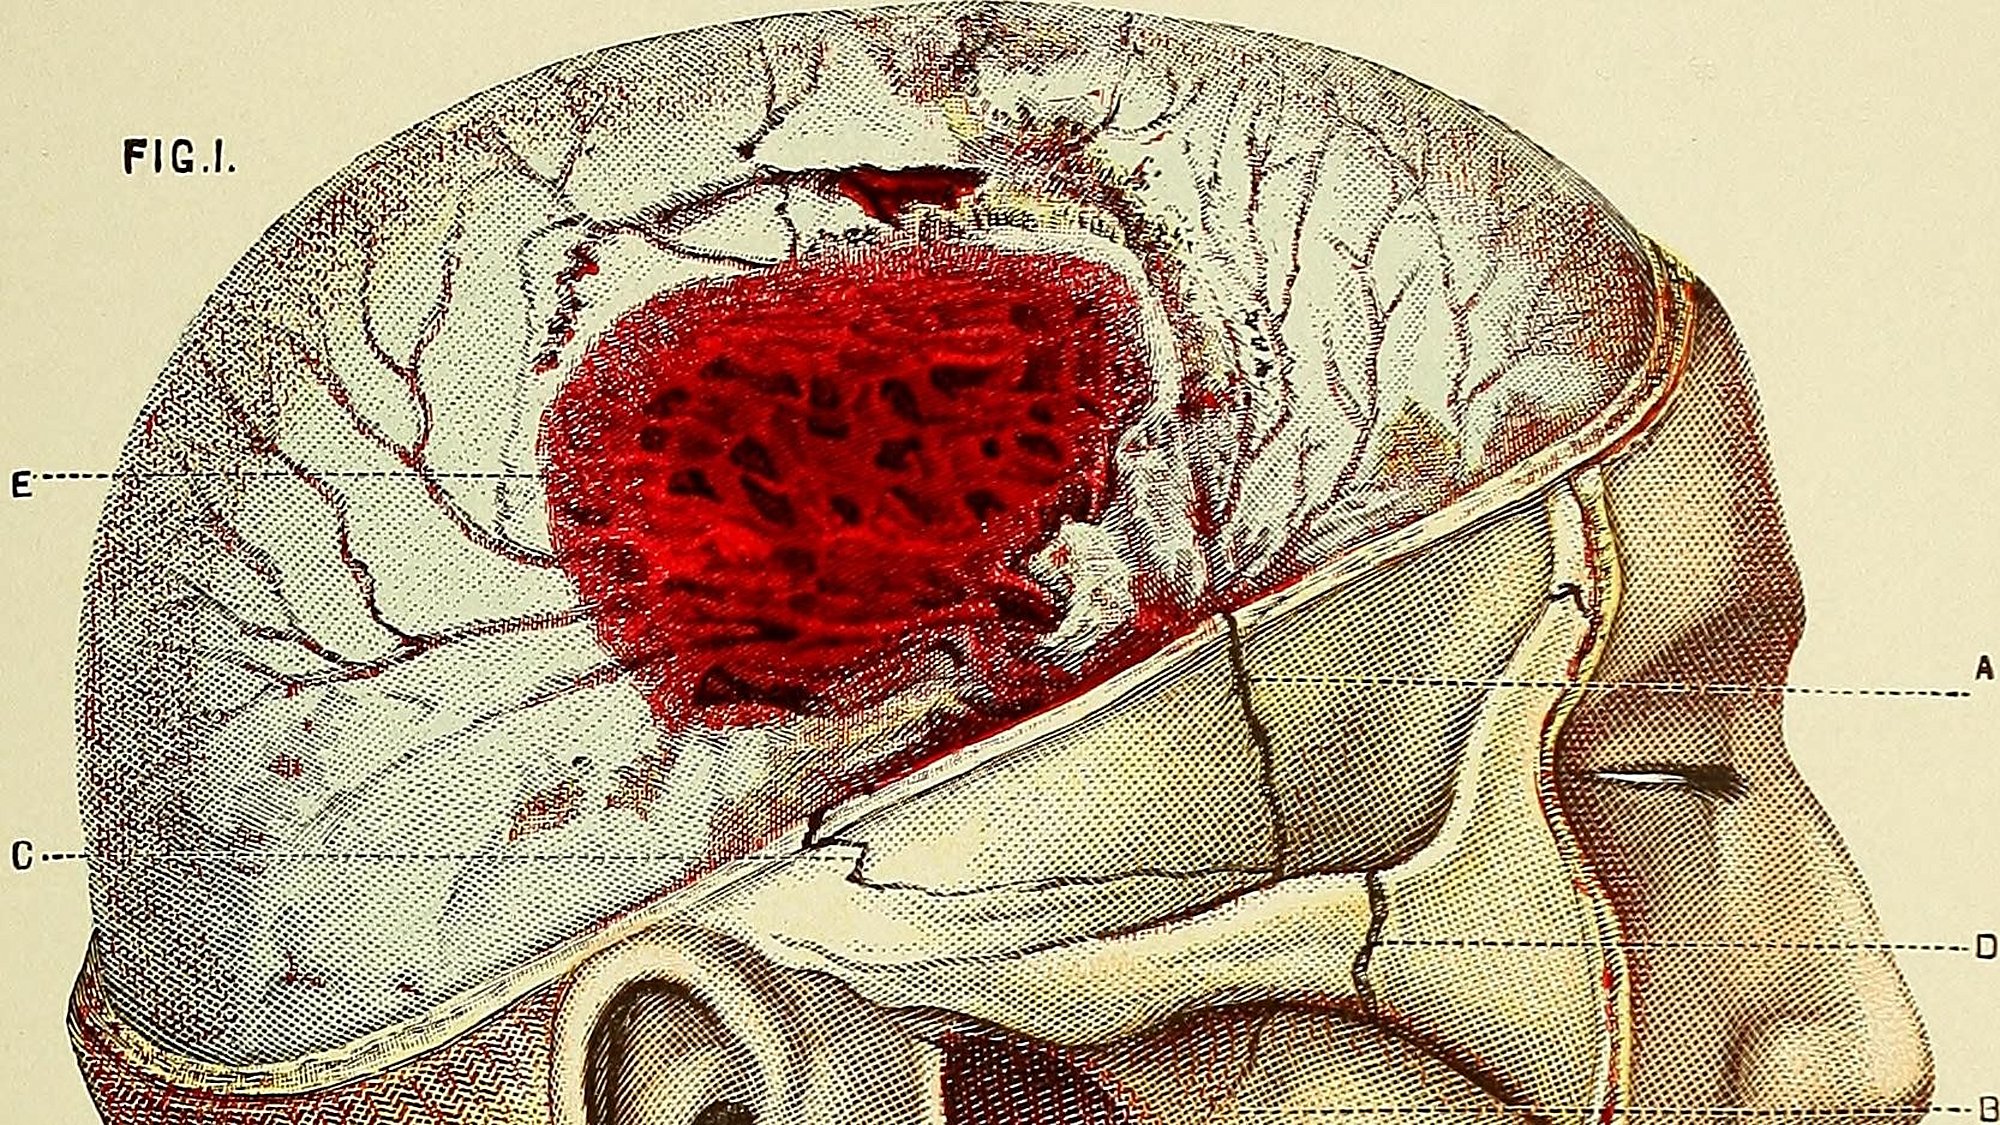

Beyin kanaması, beyin parankiminde oluşan kanamadır ve iskemik inmeden sonra en sık görülen ikinci inme (felç) türüdür. En sık görülen nedenler arasında yüksek tansiyon, serebral amiloid anjiyopati, vasküler malformasyonlar ve antikoagülan tedaviler yer alır. Kanamanın yeri ve derecesine bağlı olarak farklı belirti ve bulgular ortaya çıkar. Semptomlar genellikle bilinçte azalma, uzuvlarda kuvvet kaybı, konuşma bozuklukları ve baş ağrılarıdır.

Klinik olarak beyin kanaması iskemik inmeden güvenilir bir şekilde ayırt edilemez, bu nedenle bilgisayarlı beyin tomografi görüntülemesinin mümkün olan en kısa sürede yapılması gerekir. Akut tedavinin bir parçası olarak sık sık artan kan basıncı ve her türlü kanama diyatezi tedavi edilmelidir. Kafa içi basıncı yükselirse, kafa içi basıncını düşürmeye yönelik önlemler alınmalıdır. Hematomun (kanın damar dışına sızması ve dokular arası boşlukta birikmesi durumu) beyin cerrahisi yoluyla boşaltılması kimi zaman gerekli olabilir.

Belirti ve Bulgular

Hastalığın belirti ve semptomları kanamanın oluştuğu yere göre değişmektedir. Semptomlar genel hatlarıyla şu şekilde sıralanabilir: